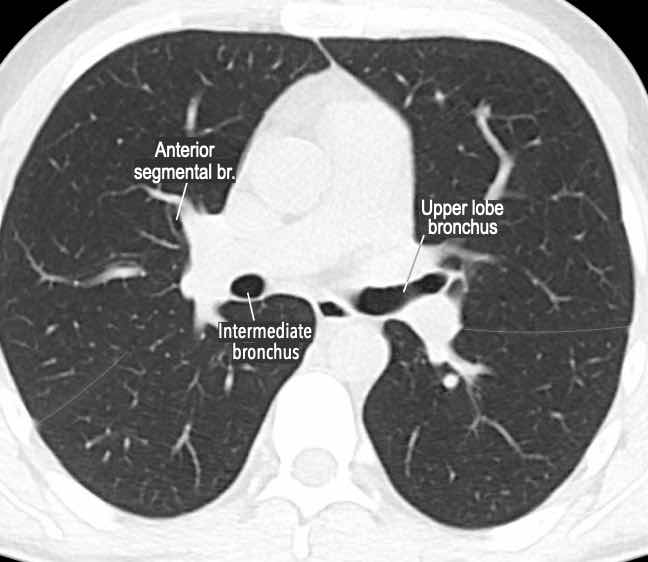

Phế quản trên CT

Cuộn qua các hình ảnh để quan sát khí quản phân chia thành phế quản chính phải và trái, sau đó tiếp tục phân chia thành các phế quản thùy và phế quản phân thùy.